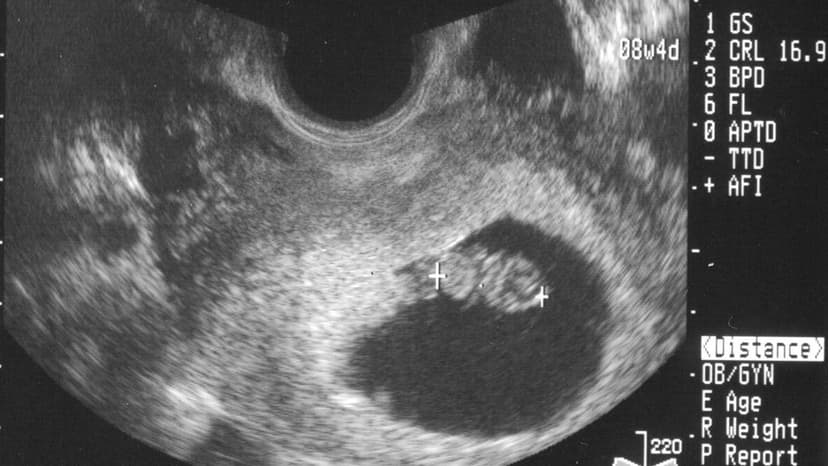

Xương mũi thai nhi thường bắt đầu hình thành rõ nét vào tuần thứ 12 của thai kỳ. Việc siêu âm đo chiều dài xương mũi thai nhi theo tuần giúp bác sĩ chẩn đoán hình ảnh và theo dõi sự phát triển tổng thể của bé.